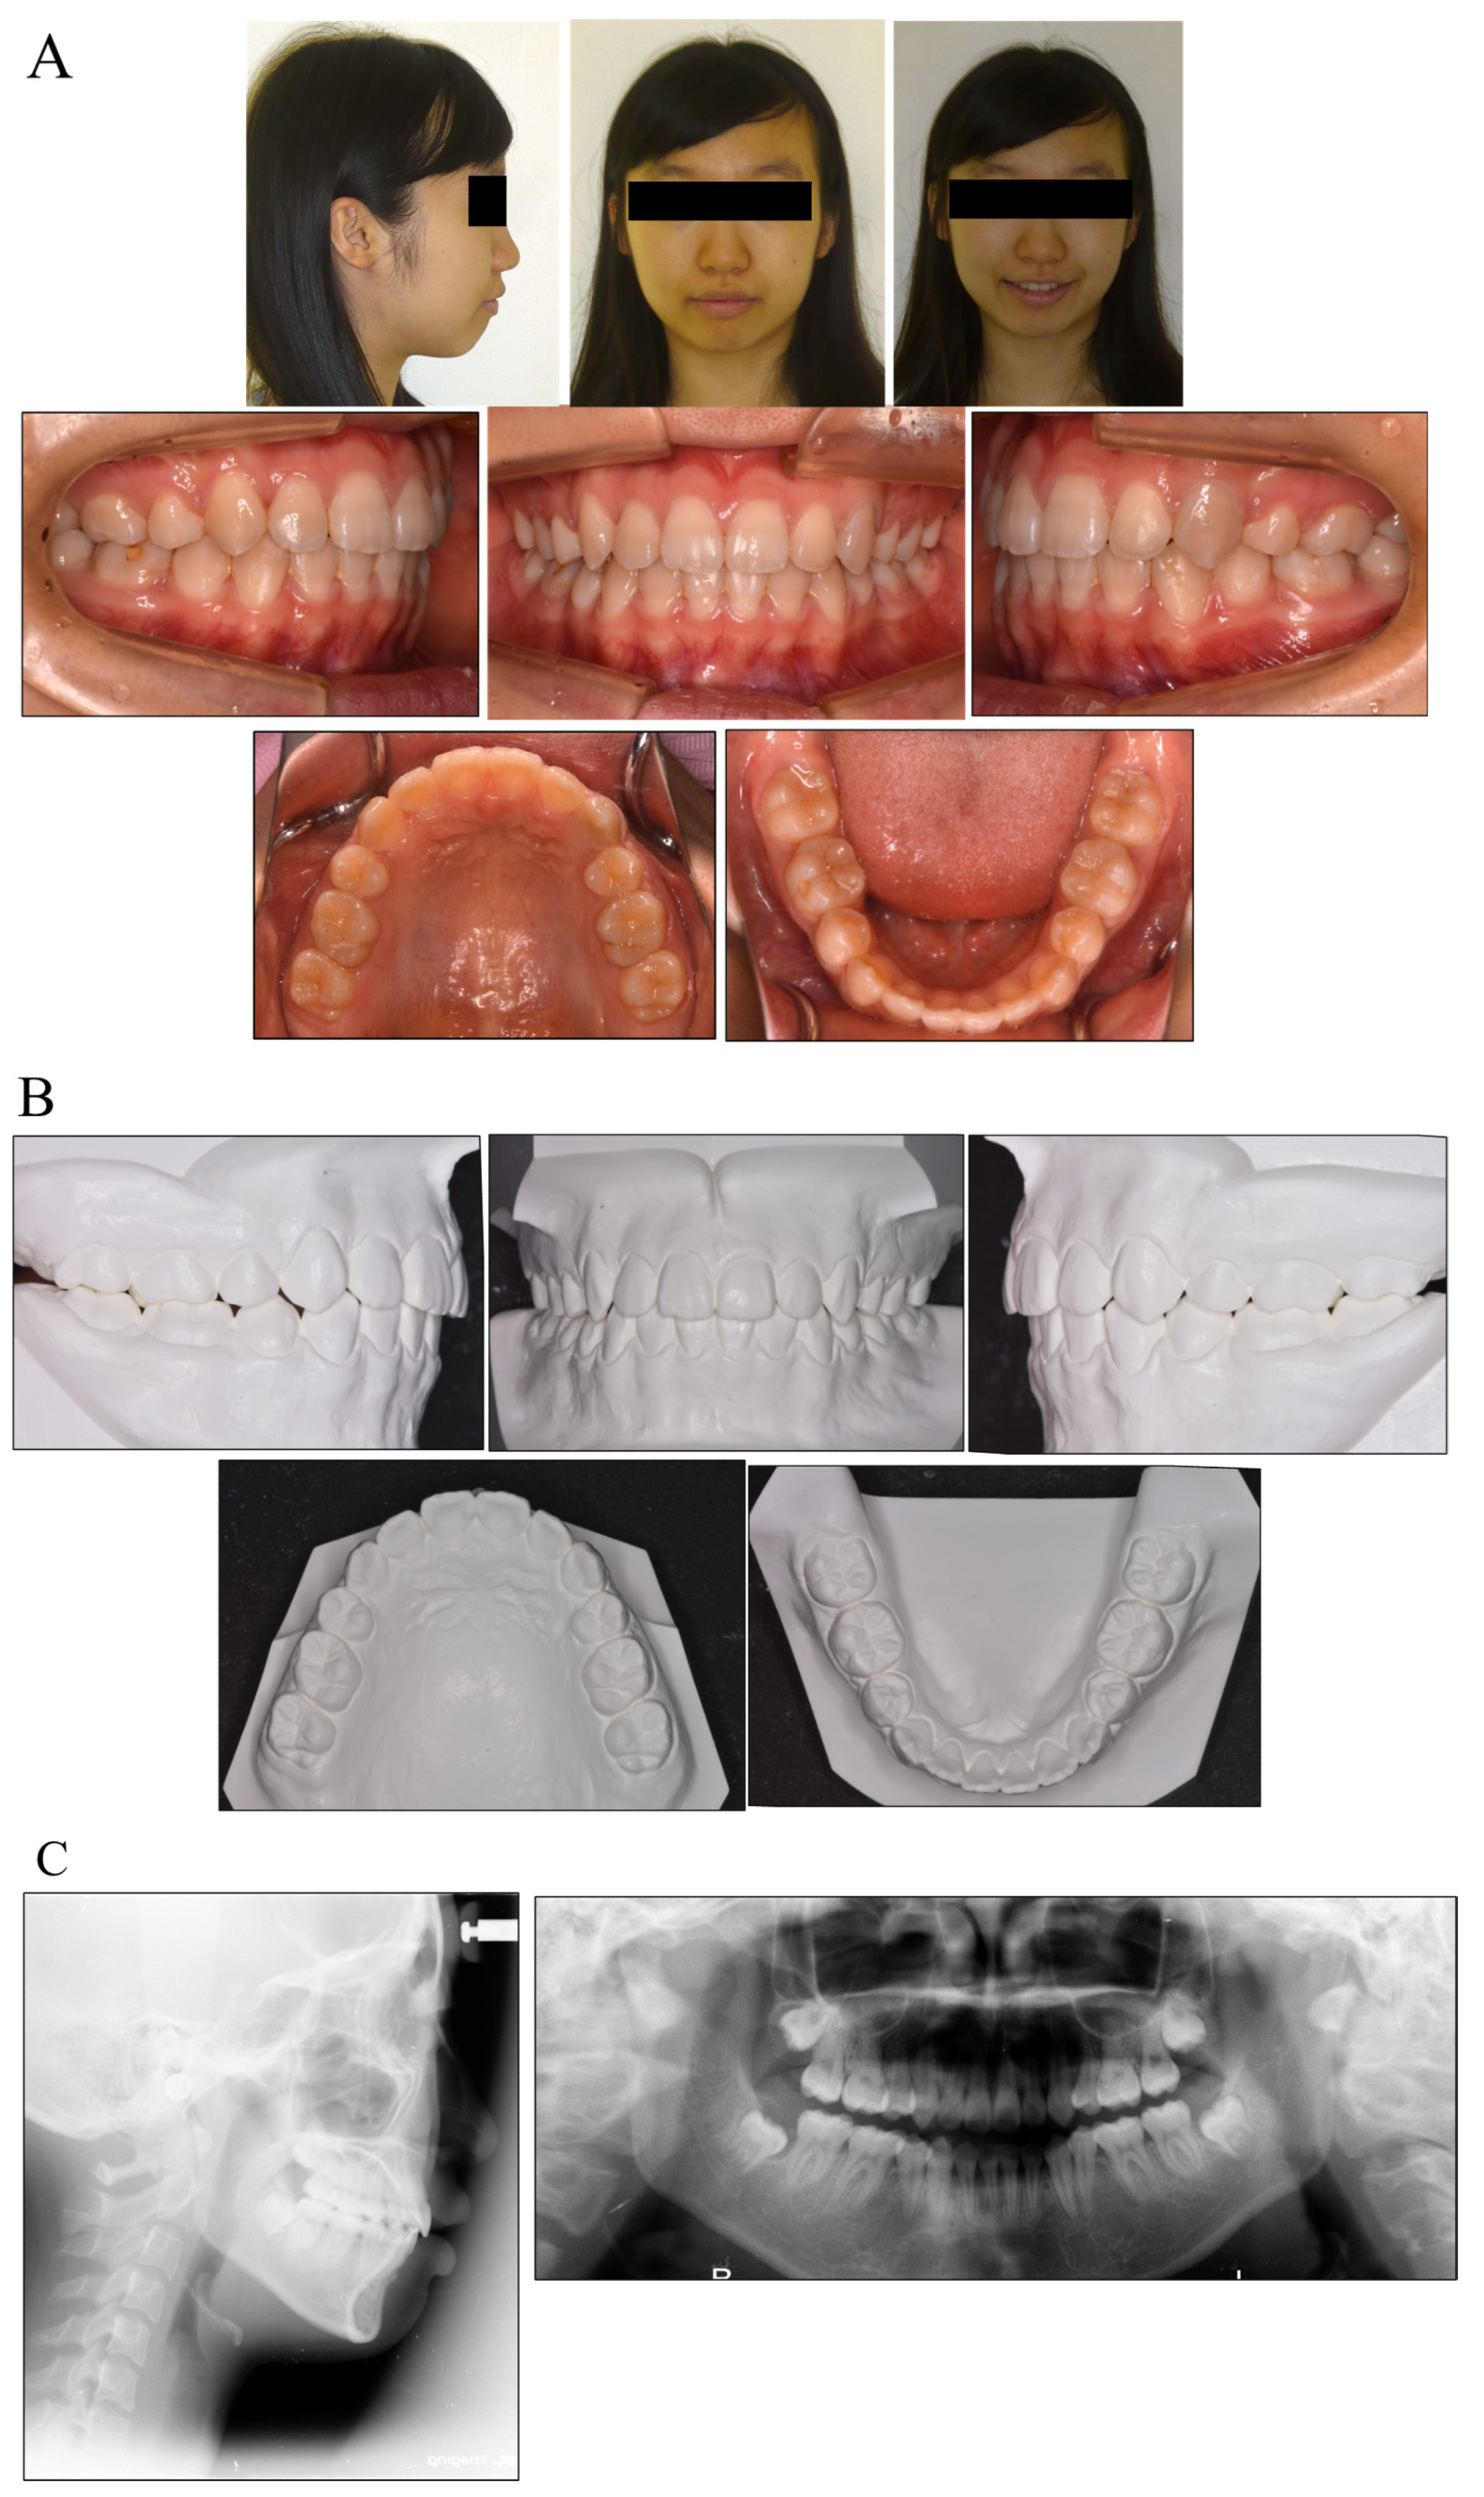

Pretreatment facial photographs revealed a convex facial profile and slight facial asymmetry, but no problems with molar relationships. In comparison with her facial midline, the maxillary dental midline was shifted 1 mm to the right. The patient had Angle Class I malocclusion with a 1.0 mm overjet and a 1.0 mm overbite. Both the maxillary and mandibular arches were irregularly aligned, with a −5.0 mm discrepancy in the maxillary arch length and a −3.5 mm discrepancy in the mandibular arch length (Figure 2). A panoramic radiograph showed that none of her third molars had erupted. The lateral cephalometric analysis indicated a normal skeletal relationship with an ANB angle of 4.7°, a slight high Frankfort mandibular plane angle (FMA) of 32.6°, and labially inclined incisors with the maxillary central incisor at a Frankfort plane angle (FH-U1) of 113.5° and a mandibular central incisor at a Frankfort mandibular incisor angle (FMIA) of 44.2° (Table 1). This diagnosis with Angle Class I malocclusion was with a bimaxillary protrusion.

Figure 2.

Facial and intraoral photograph (A), dental casts (B) and radiographs ((C) lateral cephalogram; panoramic radiograph) of pretreatment (patient is 15 years old).